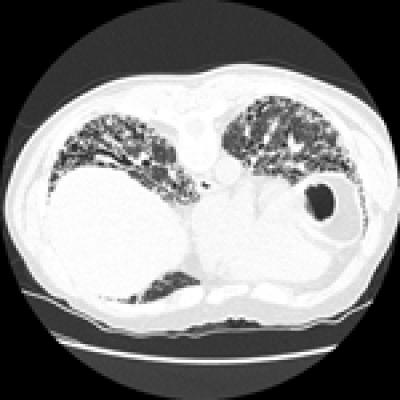

IPF, which affects nearly 100,000 Americans, slowly steals the ability to breathe freely. Its cause or causes are not clear, which is why it is called "idiopathic." Over time it leads to the buildup of scar tissue in the lungs that accumulates in a distinctive honeycomb pattern that can be seen on biopsy or CT scan. It is known as an interstitial lung disease because it affects the tissue around the air sacs in the lungs.